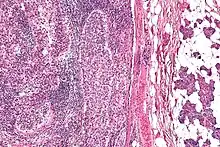

Micrograph of a sebaceous carcinoma (left of image) metastatic to the parotid gland (right of image). H&E stain.